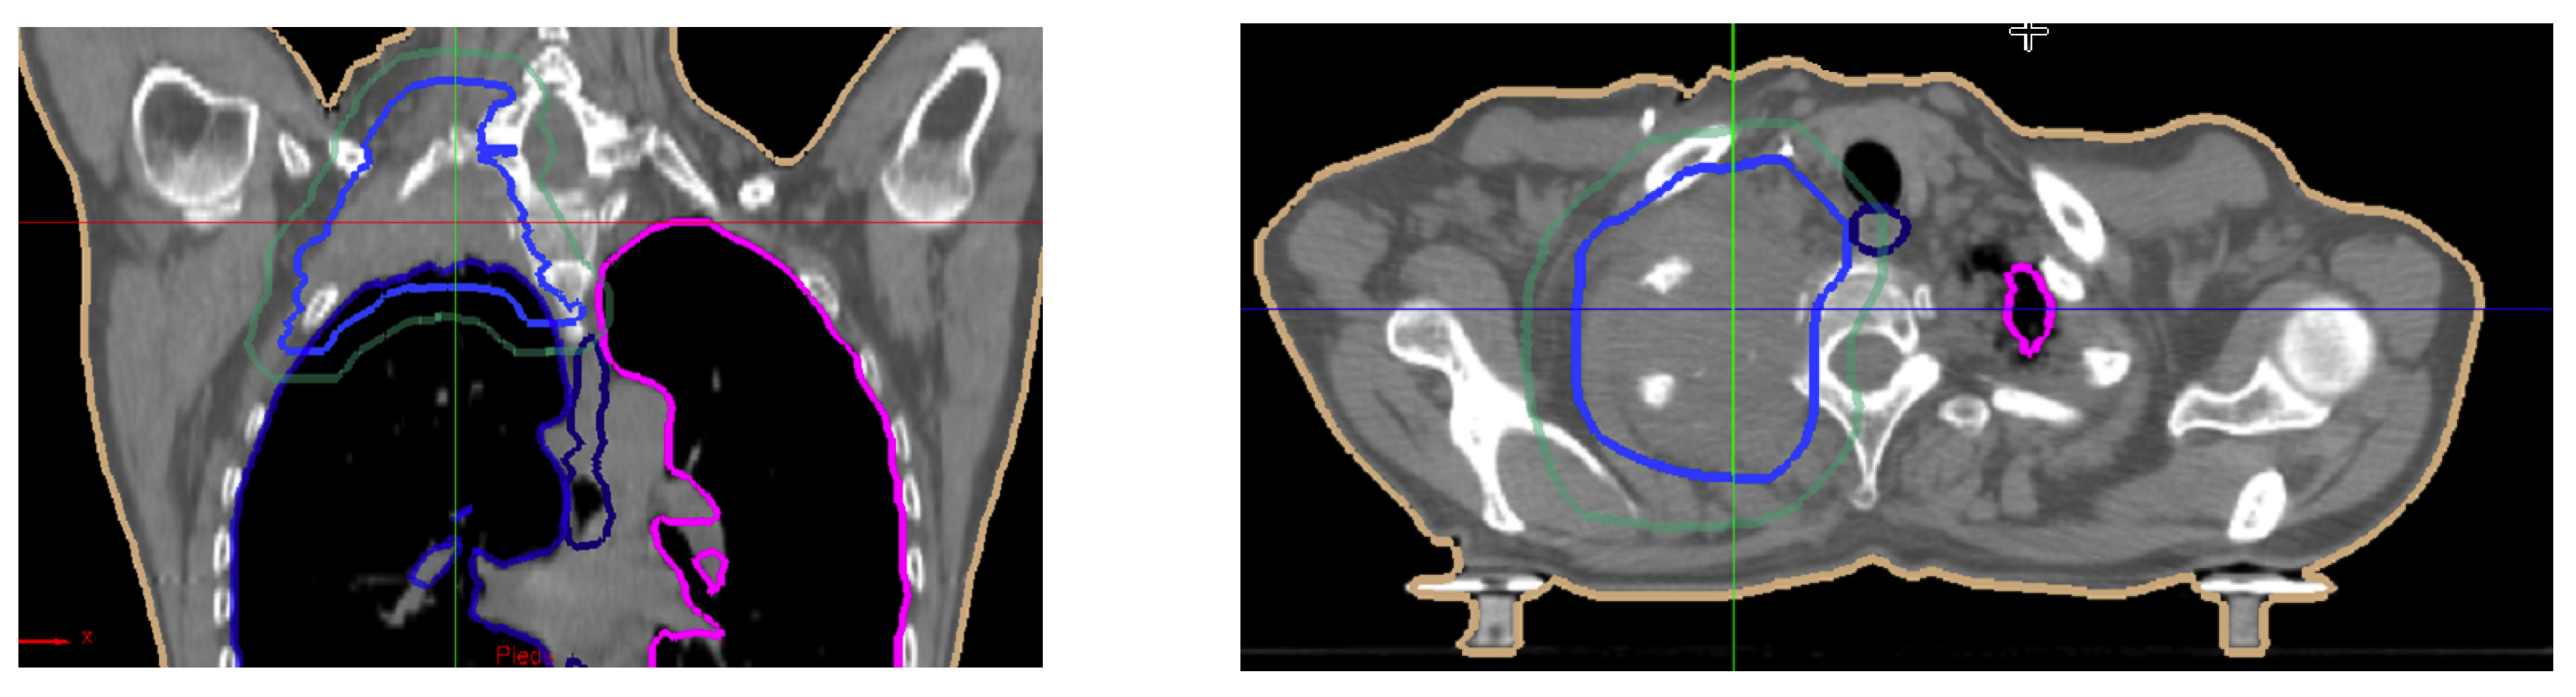

5. Illustrations